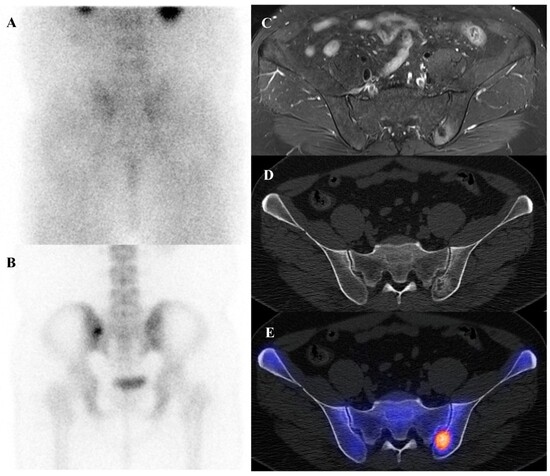

Clinical, Radiological, and Pathological Features of Intraosseous Hibernoma: A Systematic Review of Case Reports and Case Series

Intraosseous hibernoma (IOH) is a rare benign tumor composed of brown adipose tissue within the bone, frequently mimicking metastatic lesions and leading to diagnostic challenges. This systematic review aimed to consolidate and analyze all published IOH cases to improve recognition and inform management. [...] Read more.

Intraosseous hibernoma (IOH) is a rare benign tumor composed of brown adipose tissue within the bone, frequently mimicking metastatic lesions and leading to diagnostic challenges. This systematic review aimed to consolidate and analyze all published IOH cases to improve recognition and inform management. A comprehensive literature search was conducted in PubMed, Web of Science, Scopus, Google Scholar, and the Cochrane Library from database inception to March 2025. Studies were eligible for inclusion if they reported histopathologically confirmed cases of intraosseous hibernoma (IOH) in human patients. A total of 62 cases from 30 studies were included. The mean age was 59.2 years, with a female predominance. Lesions were most frequently located in the pelvis and spine and were typically identified incidentally during cancer staging or imaging performed for unrelated indications. Imaging often revealed sclerotic patterns on computed tomography (CT), hyperintense signals on magnetic resonance imaging (MRI) T2-weighted and short tau inversion recovery (STIR) sequences, and mild to moderate uptake on 18F-fluorodeoxyglucose positron emission tomography/computed tomography (18F-FDG PET/CT). Immunohistochemistry consistently showed S100 protein positivity. Most patients underwent biopsy and were managed conservatively, with no cases of malignant transformation reported. IOH is a benign entity with distinctive radiologic and immunohistochemical features that may mimic malignancy. Awareness of its presentation can reduce misdiagnosis and unnecessary interventions, supporting biopsy-based confirmation and conservative management in most cases. Full article